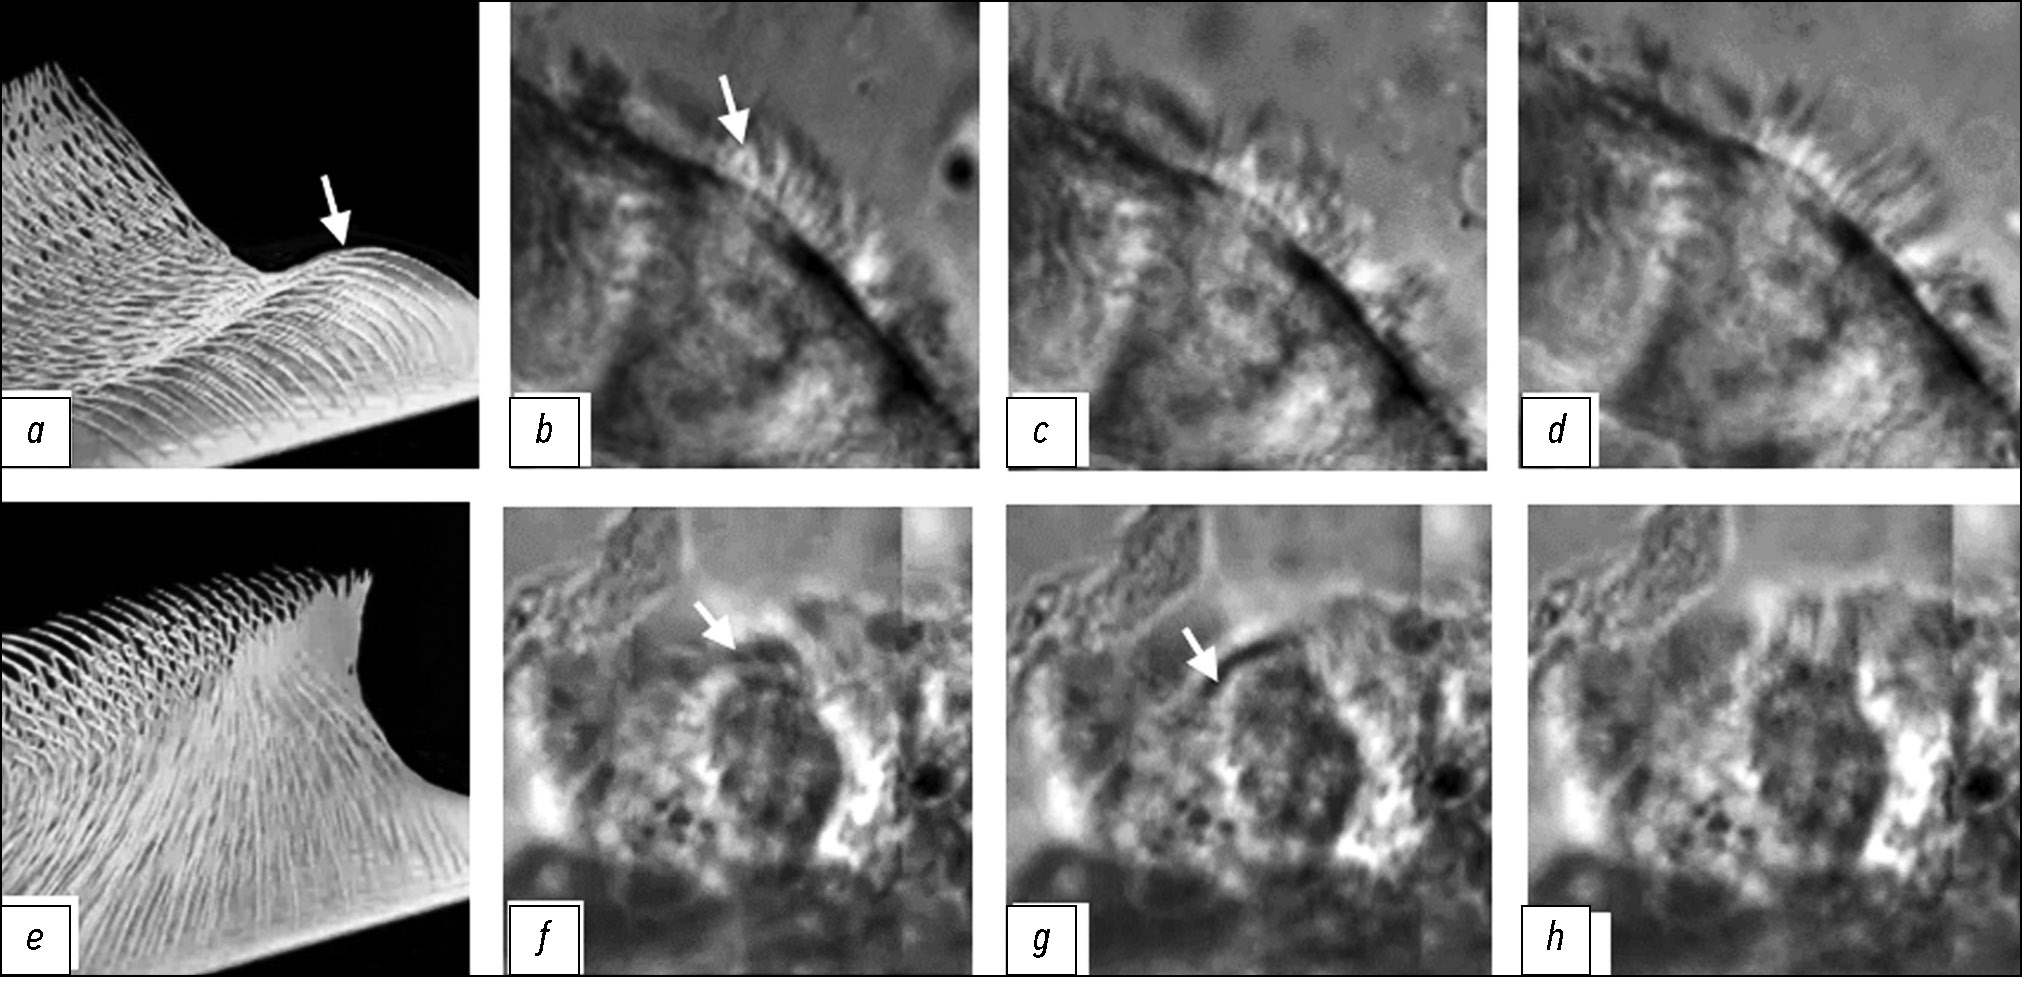

The frame-by-frame analysis of video recordings revealed that in newborn rats, the rapid beating of short cilia had a poorly defined wave-like pattern and was insufficiently synchronized (Fig. 3, b–d). The appearance of typical ciliary beating cycles with distinct effective and recovery phases occurred by day 14 of postnatal development. Between 14 and 26 months, the wave-like character of long ciliary movement in the recovery phase was most pronounced (Fig. 3, f–h). These observations were confirmed by the phase analysis of ciliary beating. In newborn rats, the effective stroke phase was minimal (16.5–16.6 ms) across all bronchial regions. By day 14 and at all subsequent ages, this parameter stabilized at 26–32 ms. Regardless of CBF, the fundamental cycle structure was preserved: the ratio of the effective stroke phase to the total cycle duration (normalized to 1.0) remained stable across all time points (0.38–0.41).

Fig. 3. Phases of ciliary beating in epithelial cells of the main bronchi in rats: a, e, diagram; b–d, f–h , frames from intravital microvideo recording; b–d, newborn rats; f–h, 26-month-old rats; a, b, f, g, recovery stroke phase, bending direction indicated by arrows; c–e, h, effective stroke phase. Objective lens, ×40.